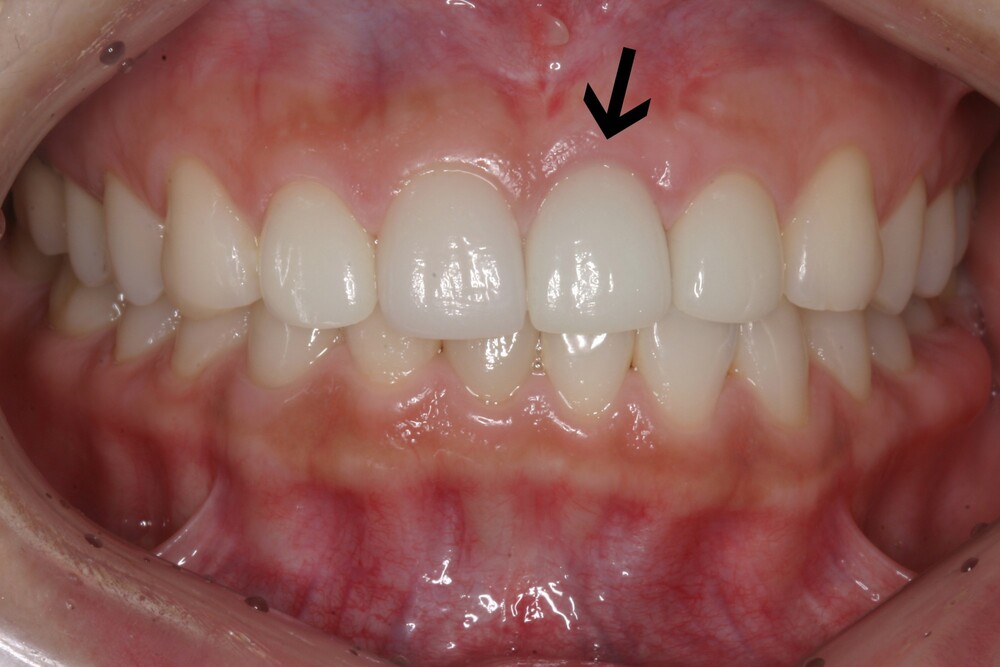

앞니는 잇몸 높이와 치아 비율이 중요해서 사진/스마일 라인까지 포함해 계획해야 합니다. 이 단계에서 임플란트 위치가 확정되면 이후 보철의 자연스러움이 크게 좋아집니다. 만약이때 거미스마일이 있는 환자가 있다면 임플란트 치료 전에 거미스마일 해결 부분을 고려해야 합니다.

(잇몸성형과 앞니임플란트 병행치료)

잇몸선을 맞추어 앞니임플란트 완성